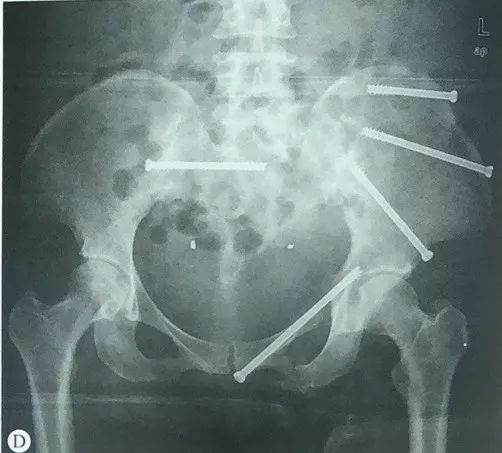

骨科微创时代 骨盆骨折不再是 大 问题 患者

早读 骨盆骨折的闭合复位经皮微创技术 医贰叁云学院 微信公众号文章阅读 Wemp

骨盆环骨折的治疗策略